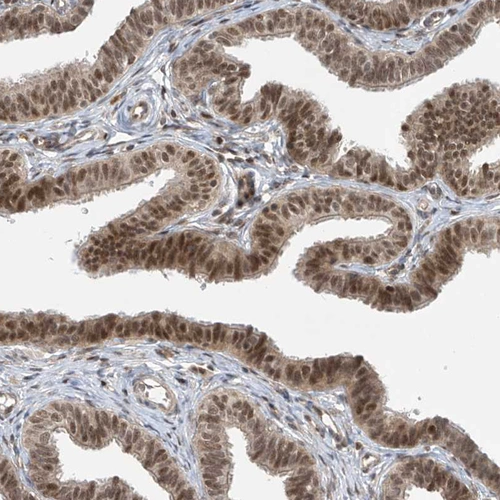

Immunohistochemical staining of human pancreas shows strong nuclear positivity in exocrine glandular cells.